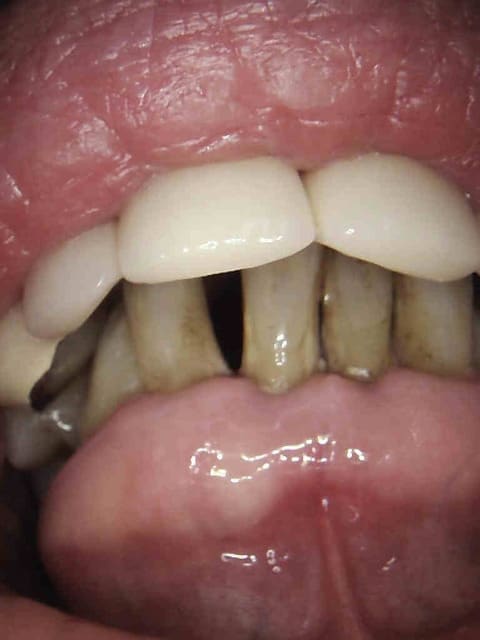

Voir cas ci dessous.

1 t0vddl - Eugenol

2 oailks - Eugenol

De toutes façons, au vu de la gueule de ses incisives, ce sera vite un complet si l'étiologie n'est pas maîtrisée.

Oui , la meilleure c'est qu'il fait partie de mes cas de radios abusives.

Toutes les radios sont abusives " sauf éventuellement la 21".

punaise mais chicot, tu bosses où pour avoir des cas comme cas? Directement depuis l'aeroport dont les patients reviennent du bled?

Je penses que si tu veux faire un concours tu vas perdre. Patient au smic pas un centime devant lui. Amuses toi. -)))))

1 f8r5uw - Eugenol

2 uqjowx - Eugenol

3 b6buap - Eugenol

4 ax5o6k - Eugenol

5 uxxr26 - Eugenol